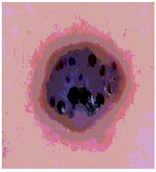

![]() | ![]() | ![]() | ![]() |

| Img1 | --- Pixel Intensity (0–255) ---> | ||

| Img2 | --- Pixel Intensity (0–255) ---> | ||

| Img3 | --- Pixel Intensity (0–255) ---> | ||

| Img4 | --- Pixel Intensity (0–255) ---> | ||

| Img5 | --- Pixel Intensity (0–255) ---> | ||

| Img6 | --- Pixel Intensity (0–255) ---> | ||

| Img7 | --- Pixel Intensity (0–255) ---> | ||

| Img8 | --- Pixel Intensity (0–255) ---> | ||

| Img9 | --- Pixel Intensity (0–255) ---> | ||

| Img10 | --- Pixel Intensity (0–255) ---> | ||